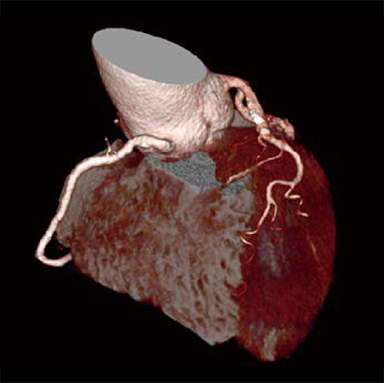

Dans les examens TDM cardiaques, les différents facteurs tels que la fréquence cardiaque et les mouvements du cœur affectent la qualité de l’image. Avec les méthodes conventionnelles de reconstruction d’image, des artères coronaires non focalisées et des artefacts causés par le mouvement peuvent apparaître, ce qui se traduit par des images ne répondant pas à la qualité attendue, ce qui peut affecter le diagnostic. Pour résoudre ces problèmes, Fujifilm a développé Cardio StillShot, qui calcule la direction et la quantité de mouvement du sujet en quatre dimensions à partir des données brutes collectées pendant les examens TDM cardiaques, et les corrige pendant la reconstruction de l’image pour obtenir une résolution temporelle effective de 28 msec.*1 La résolution temporelle effective contribue à améliorer la capacité de diagnostic en fournissant des images cliniques focalisées de haute définition avec moins d’artefacts de mouvement, même chez les patients ayant une fréquence cardiaque élevée.

Cardio StillShot : OFF

ON